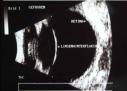

Das Augen-Ultraschallgerät Sonomed B5500+ ein Ultraschall-Querschnitt des Auges Ultraschallquerschnitt des Kammerwinkels